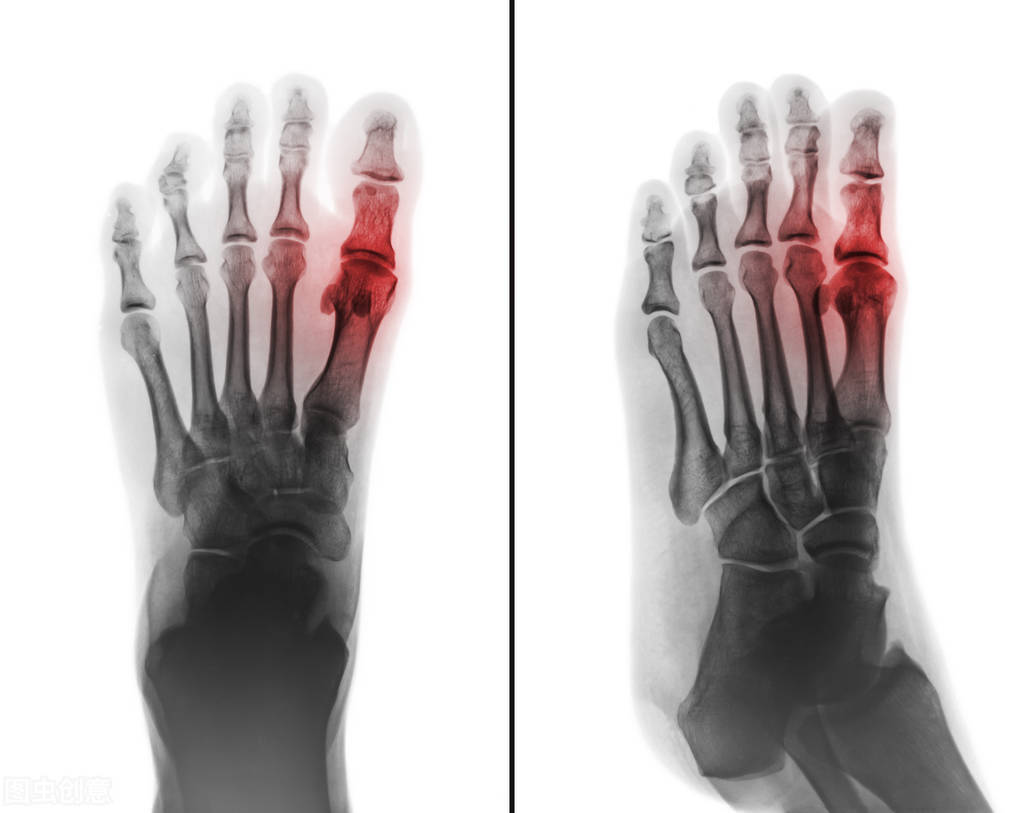

症状:左侧脚的大脚趾肿、痛 , 痛得特别厉害 , 走路时左脚的大脚趾不敢着地 , 也不敢用手碰 , 他的疼痛是有种烧灼感的疼痛 , 晚上睡不好觉 , 有时大脚趾疼 。 其它的饮食、大小便都还正常 , 舌脉是舌边红 , 脉浮紧 。

证候分析:这个患者当时是痛风的急性发作期 , 有烧灼感的疼痛 , 红肿热痛 , 舌红 , 脉浮紧 , 都是风湿热的表现 。